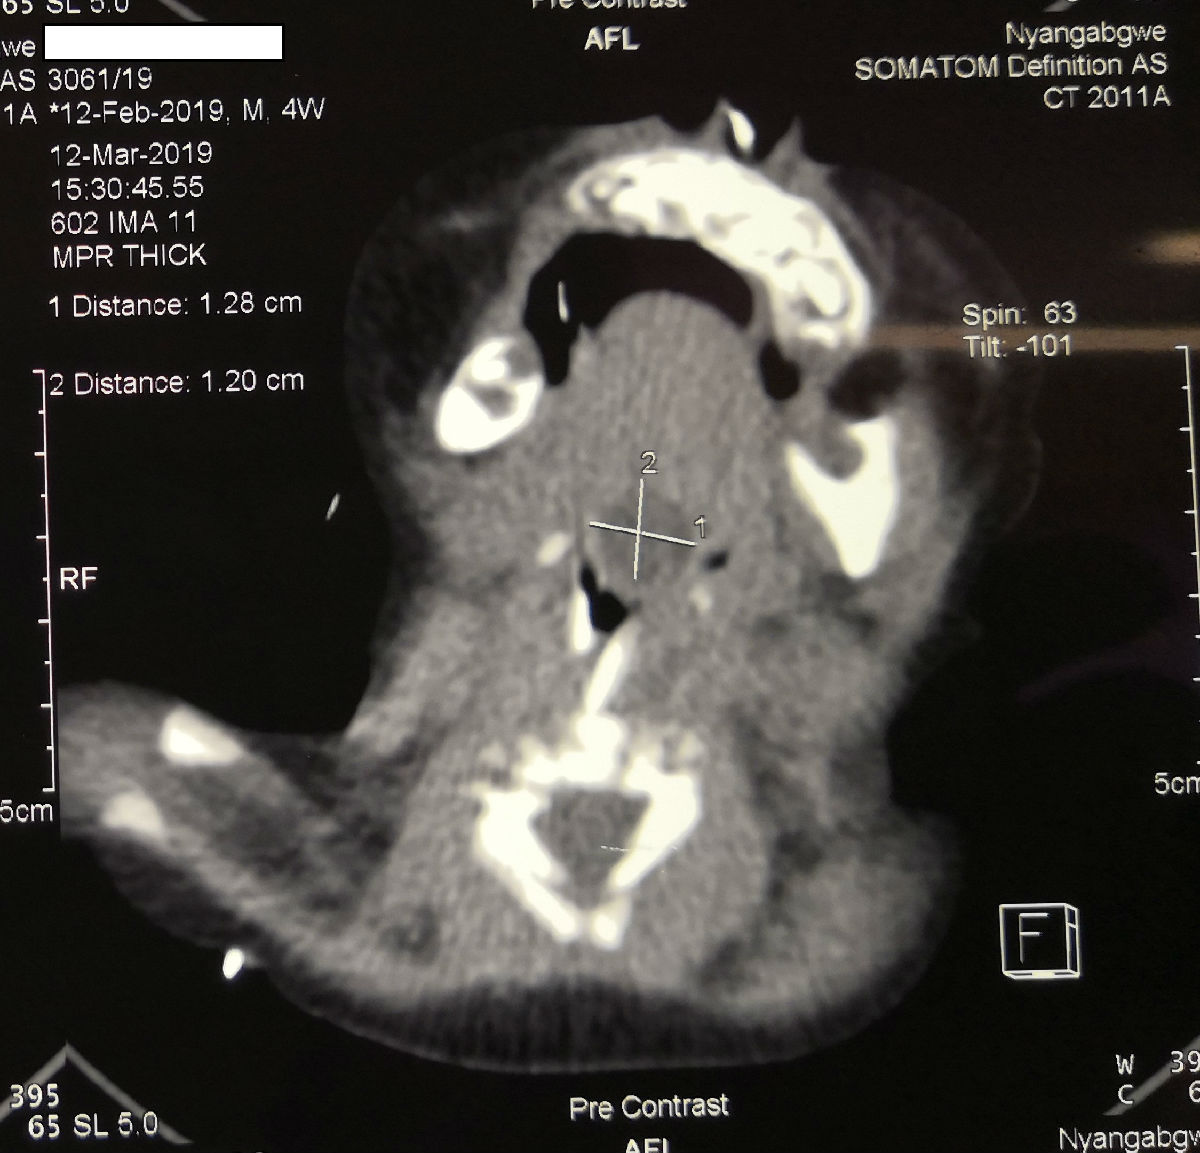

陈希杭是我院选派的第15批援博茨瓦纳医疗队哈博罗内分队队员之一。前不久他为一位特殊患者进行了手术。这是一名不到3个月大的婴儿,因为在舌根部长了一个巨大的囊肿,呼吸困难,如果不及时处理,可能随时都有生命危险,患者的父母为此找了多家医院,但是当地医生都拒绝为其手术。陈希杭对患者进行检查之后,发现肿物位置很深,而且十分巨大,占据了患者的整个喉咙,再加上当地医院缺乏等离子刀等手术器械,因此手术难度很大。

陈希杭凭借多年的经验,想到可以利用吸引器套上塑料吸引器管,制作成一个电凝手术器械,并且利用小儿支撑喉镜,尽可能微创地将舌根的巨大肿物切除。最终,经过一个多小时的努力,手术成功完成。三天后,患者顺利拔除气管套管,并且发出了清亮的哭声。患者的家长听到哭声之后,非常高兴。当地医生也纷纷称赞中国医疗队,称这是“一次不可思议的手术!”